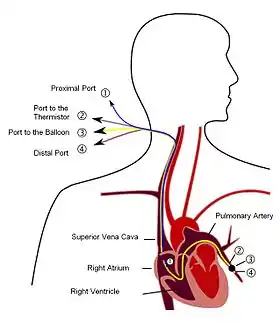

Right heart catheterization

Although pulmonary arterial pressure (PAP) can be estimated on the basis of echocardiography,[62] pressure measurements with a Swan-Ganz catheter inserted through the right side of the heart provide the most definite assessment.[42] Pulmonary hypertension is defined as a mean PAP of at least 20 mm Hg (3300 Pa) at rest, and PAH is defined as precapillary pulmonary hypertension (i.e. mean PAP ≥ 20 mm Hg with pulmonary arterial occlusion pressure [PAOP] ≤ 15 mm Hg and pulmonary vascular resistance [PVR] > 3 Wood Units).[55] PAOP and PVR cannot be measured directly with echocardiography. Therefore, diagnosis of PAH requires right-sided cardiac catheterization. A Swan-Ganz catheter can also measure the cardiac output; this can be used to calculate the cardiac index, which is far more important in measuring disease severity than the pulmonary arterial pressure.[11][63] Mean PAP (mPAP) should not be confused with systolic PAP (sPAP), which is often reported on echocardiogram reports. A systolic pressure of 40 mm Hg typically implies a mean pressure of more than 25 mm Hg. Roughly, mPAP = 0.61•sPAP + 2.[64]